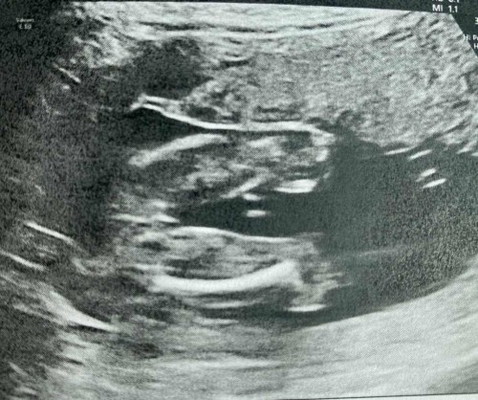

แม่ๆ ช่วยดูเพศน้องให้หน่อยค่ะ

คุณหมอยังไม่ฟันธง แต่แม่อยากซื้อของเตรียมให้น้องแล้วค่ะ😄 (21w)

ฝากดูหน่อยจ้า บ้านนี้หมอบอก ลูกสาว 80% ลูกสาวหรือลูกชายค่ะ

ไม่ค่อยชัดเลยค่ะ น่าจะ ญ ไหมคะ